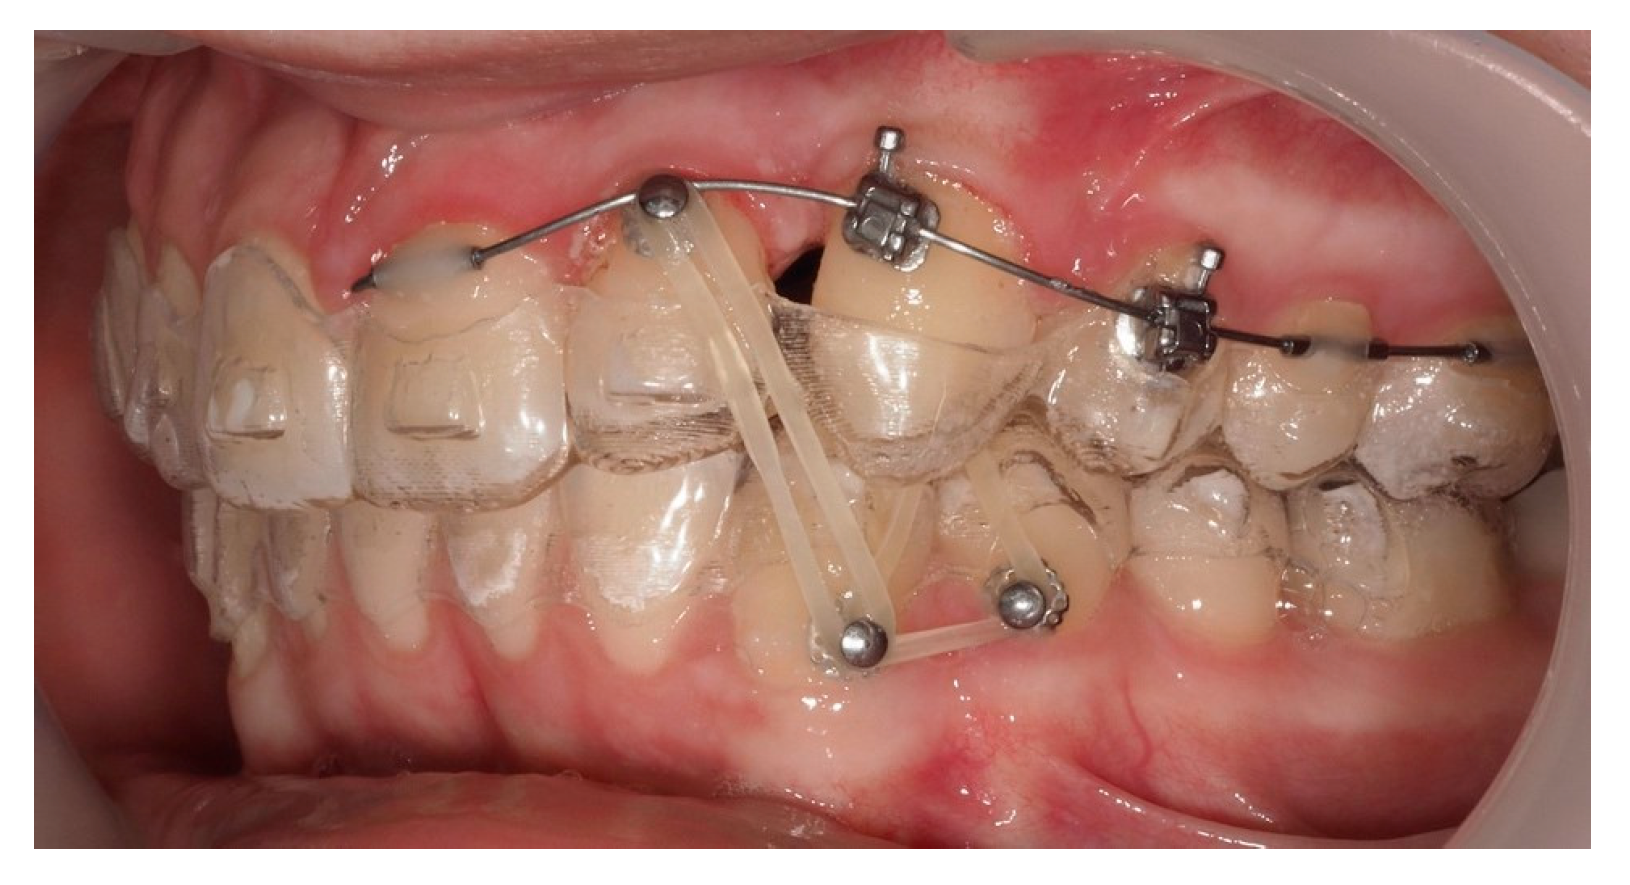

Approximately 7 months later, a palatal mini-implant was placed between teeth 24 and 25, serving as stable anchorage for distal traction using an elastic chain, which was replaced monthly (Figure 15). This movement positioned the canine away from the lateral incisor root. Aligners were customized and adjusted throughout treatment.

Figure 15.

Adjusted aligners, palatal mini-implant, and elastic chain used for distalizing the canine; 7 months after the surgery.

Following initial distalization, a sectional fixed appliance was bonded from tooth 11 to 26. On tooth 24, a bracket with a metallic ligature was used to support Class II elastics. Mini-tubes were bonded on teeth 22, 25, and 26, and the aligners were trimmed accordingly (Figure 16). A ligature wire connected the palatal button on the canine to a 0.014” nitinol archwire (Figure 17).

Figure 16.

Sectional fixed appliance from teeth 11 to 26, with support for Class II elastics to improve sagittal relationship; 14 months after the surgery.

Figure 17.

Ligature wire attached to a 0.014” nitinol archwire on the palatal surface of the canine; 14 months after the surgery.

During vestibular traction, gingival removal was required. The canine presented mesial tipping and rotation. In the 14th month after the surgery, a bracket was bonded to tooth 23, following its inclination. A button was bonded on tooth 33 and connected by elastic to tooth 22 to stabilize the vertical position. Another elastic with a Class II vector was attached from the bracket on tooth 24 to a precision cut in the lower aligner (Figure 18).

Figure 18.

Vestibular traction of the canine, gingival removal, and elastic use for vertical stabilization; 14 months after the surgery.